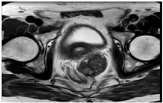

患者遂于2018年6月11日行肝左外叶切除术。术后病理符合直肠癌肝转移。术后患者恢复顺利,经与肿瘤科商议,在2018年7月2日至2018年11月9日予以奥沙利铂+卡培他滨化疗6次。随后定期随访,患者似乎对癌胚抗原指标较敏感,所以重点关注了此项指标。CEA分别为2.33 ng/ml (2018年7月3日)、4.54 ng/ml (2018年10月8日)、15.66 ng/ml (2018年11月12日,肝转移切除术后5个月)。此时患者出现癌胚抗原指标升高,完善胸部、全腹部增强CT未见转移征象,建议患者行PET-CT检查。但患者因经济因素拒绝,遂嘱其3个月后再次复查。患者因个人因素于8个月后来院检查,癌胚抗原为3.35 ng/ml (2019年6月11日,肝转移切除术后1年),胸腹部CT未见转移征象。患者1年后主诉会阴部疼痛、坠胀,完善癌胚抗原为9.9 ng/ml (2020年7月14日,直肠癌术后近7年,肝转移切除术后2年),完善盆腔MR检查(图4、图5)示尾骨前肿块,考虑转移性病灶,侵及左侧精囊腺、前列腺可能性大(2020年7月14日)。